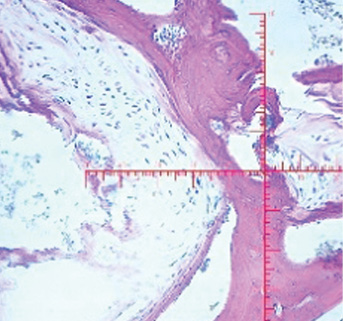

Микроскопический вид (ув. 40) |

Контрольный сустав (правый): наблюдается ограничение движений в суставе, глубина кратера «минус-ткань» составляет 2/3 толщины, края не сглажены, граница между новообразованной тканью и сохранённым хрящом прослеживается чётко. Микроскопически субхондральная костная пластинка имеет искривление в сторону субхондральной кости, обнаруживаются признаки ремоделирования хрящевой ткани, что указывает на частичное восстановление структуры хряща.

1-я экспериментальная группа (левый сустав): наблюдается ограничение движений в суставе, определяется «минус-ткань», составляющая около 2/3 толщины сформированного дефекта, с ровными гладкими краями, граница между новообразованной тканью и сохранённым хрящом прослеживается чётко. Микроскопически дефект полностью заполнен молодой хрящеподобной тканью, образованной хондробластами и оксифильным межклеточным веществом. Надхрящница состоит из 2 слоёв: наружный (волокнистый) и внутренний (хондрогенный). Рост хряща происходит по аппозиционному типу.

2-я экспериментальная группа (левый сустав): определяется ограничение движений в суставе, «минус-ткань», составляющая 1/3 толщины кратера дефекта, с ровными гладкими краями, граница между новообразованной тканью и сохранённым хрящом прослеживается чётко. Микроскопически полость дефекта полностью заполнена новообразованной молодой хрящеподобной тканью. Хондробласты более интенсивно пролиферируют, они более дифференцированы, лакуны располагаются теснее. Надхрящница полностью сформирована. Наблюдается интенсивный рост хряща по аппозиционному типу.

3-я экспериментальная группа (левый сустав): определяются незначительные ограничения движений в суставе, а также «минус-ткань», составляющая 1/4 толщины сформированного дефекта, с ровными гладкими краями, граница между новообразованной тканью и сохранённым гиалиновым суставным хрящом прослеживается чётко. Микроскопически полость дефекта заполнена хрящеподобной тканью с наличием лакун и межклеточного вещества. Отмечается пролиферация хондробластов и их дифференцировка. Хрящеподобная ткань плотно сращена со стенками полости, фиброретикулярная ткань не обнаружена.

За 3 мес во всех группах произошли макро- и микроскопические изменения, отражённые в табл. 2.

Таблица 2. Макро- и микроскопическая оценка спустя 3 мес от начала эксперимента

Table 2. Macro- and microscopic evaluation after 3 month from the start of the experiment